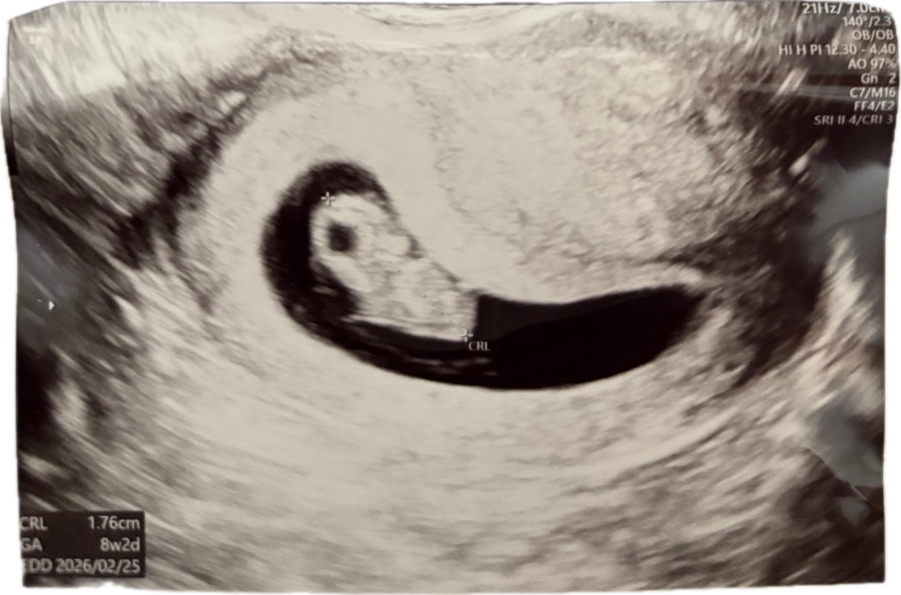

| 가슴 떨리는 임신 이야기를 공유해 주세요. | 인공수정에서 실패하고, 시험관을 시작했는데 첫 시도에서 임신테스트기 두 줄을 보게 되었을 때 정말 기뻤습니다. 순간 너무 행복했고, 아직도 그 감동이 생생합니다. 가끔은 “인공수정을 건너뛰고 바로 시험관을 했다면 더 빨랐을까?” 하는 아쉬움도 있지만, 첫 시도만에 성공했다는 사실만으로도 큰 축복이라고 생각합니다. |

| 치료 도중 느꼈던 가장 기뻤던 순간과 절망적인 것들은 무엇인가요? 잊지 못할 경험이 있나요? | 가장 절망적이었던 순간은 난자 채취 준비 기간에 갯수가 많이 나오지 않았던 것과, 채취 당일에 이미 두 개의 난자가 터져버렸다는 사실을 알았을 때였습니다. 앞이 캄캄해졌던 기억이 있습니다. 그럼에도 불구하고 두 개의 배아가 동결되었다는 결과를 들었을 때는 희망을 다시 붙잡을 수 있었고, 결국 임신에 성공했을 때의 기쁨은 말로 표현할 수 없었습니다. |